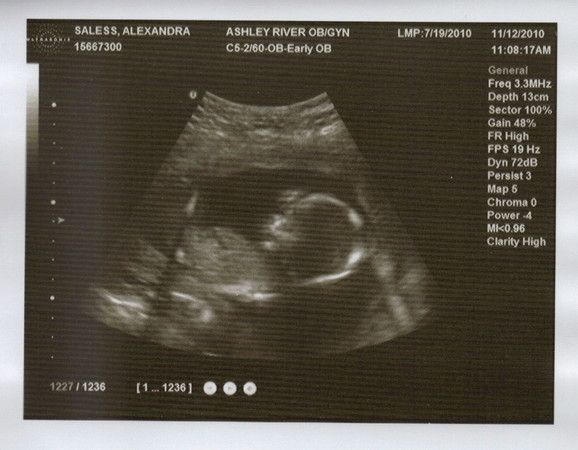

16W 4T Lexabailey's zweites US-Bild!

12.11.2010

Herzschlag war 143 bpm

So wie es aussieht ist es ein Maedchen (zu 95%)